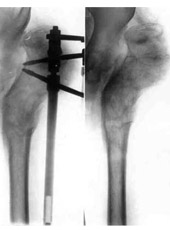

Schanz-Ilisarov's operation with elongation of hip.Schanz-Ilisarov's operation with elongation of hip.

Schanz-Ilisarov's operation with elongation of hip.

Schanz-Ilisarov's operation with elongation of hip.Dismantling of Ilisarov's apparatus.